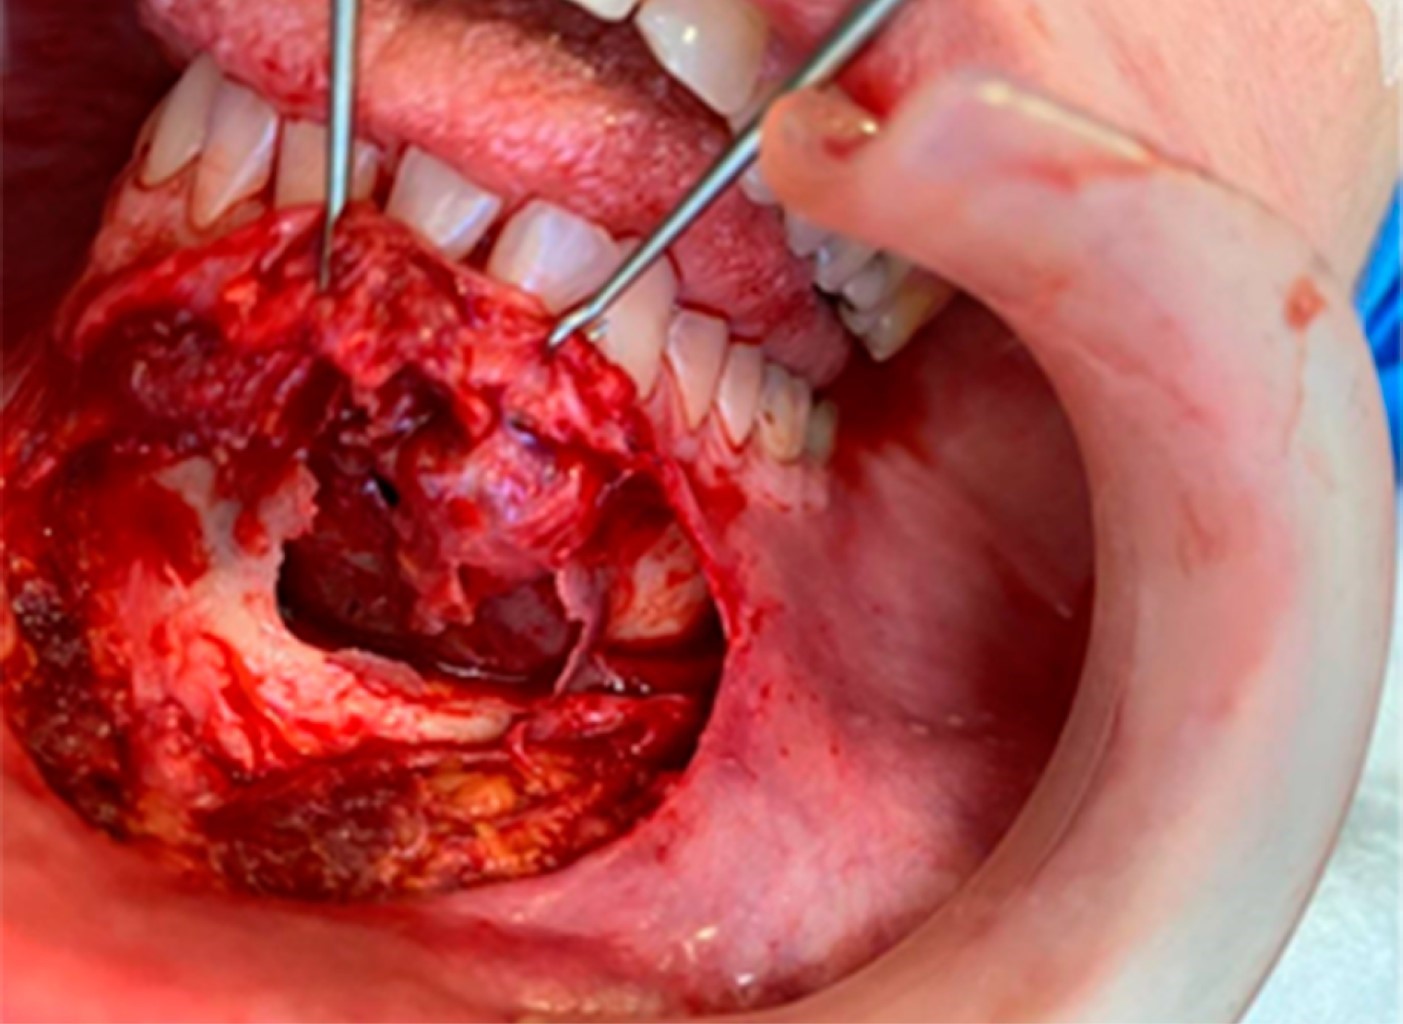

Ante este diagnóstico, la paciente optó por el tratamiento quirúrgico bajo anestesia general para la enucleación de la lesión y la ostectomía periférica. El procedimiento se realizó con infiltración de anestesia local con lidocaína al 2% en la región del surco mandibular anterior, incisión de Wassmund, con desprendimiento mucoperióstico y entre los dientes 35 a 41, con exposición total de la lesión (Figura 3).

Posteriormente, se realizó la enucleación de la cápsula quística mediante legrado local y ostectomía periférica para la extirpación completa de la lesión, con el fin de minimizar una posible recidiva de la misma (Figura 4).